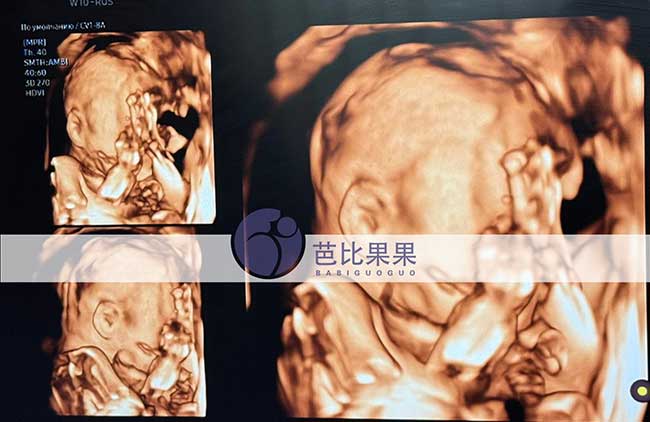

吴先生到乌克兰匹配的试管妈妈如期来做四维彩超啦!胎宝宝各项发育指标都稳稳达标,健健康康茁壮成长,每一次产检都是满心欢喜,静待可爱小天使平安到来。

吴先生到乌克兰匹配的试管妈妈如期来做四维彩超